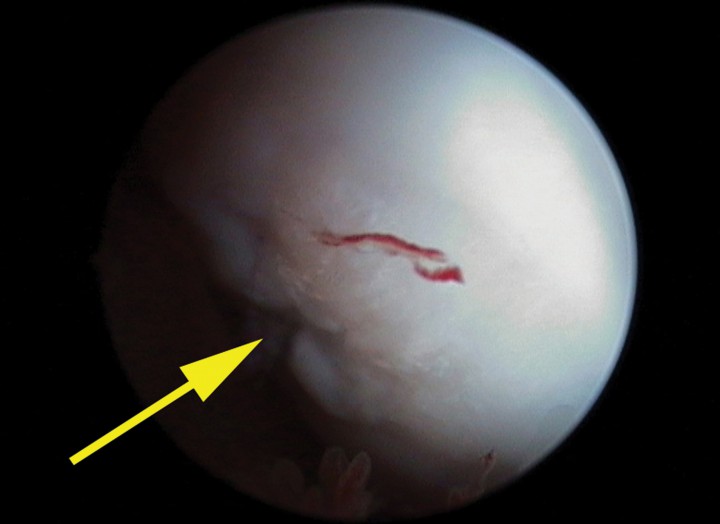

Gracias a la realización de esta técnica, se pudo confirmar el diagnóstico presuntivo realizado previamente de forma radiológica[ Altónaga JR. Manual de exploración artroscópica de la rodilla canina. Ed. Universidad de León. 1998. ] (Fig. 3). Mediante la exploración artroscópica se percibieron unas lesiones condrales que llegaban al hueso subcondral en ambos cóndilos femorales laterales. Junto a dichas alteraciones se hallaron colgajos cartilaginosos unidos todavía al cartílago articular adyacente.

<p>Imagen artroscópica del cóndilo lateral del fémur derecho mostrando la lesión (flecha amarilla).</p>

Imagen artroscópica del cóndilo lateral del fémur derecho mostrando la lesión (flecha amarilla).